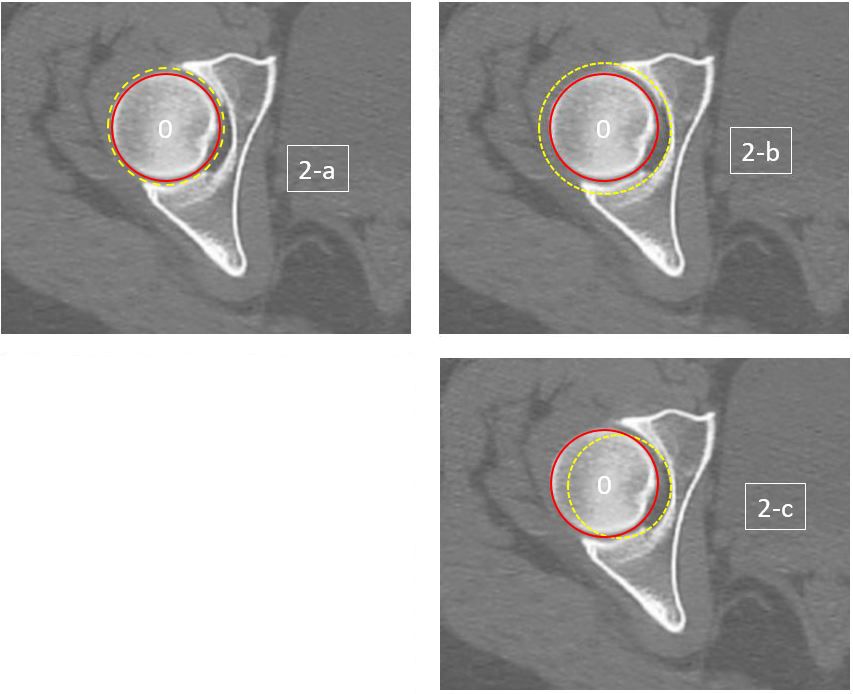

This is the foremost goal of prosthetic reconstruction of the hip. Using 100 CT scans, Bonnin et al. [14] quantified the acetabular offset and analysed the displacement of the hip’s centre of rotation, according to whether positioning was ‘conventional’ (cup in contact with the quadrilateral lamina) or ‘anatomical‘ (cup placed in the centre of the articular area of the hip) (Fig. 2). Medial displacement of the centre of rotation was 1.6 mm ± 1.2 with anatomical positioning and 4.8 mm ± 1.9 with conventional positioning (p<0.0001).

Meermans et al. [15] analysed the impact of reaming technique on displacement of the hip’s centre of rotation. They demonstrate that gradual or sequential reaming, using reamers of a progressively larger size and starting from the acetabular depression, displaces the centre of rotation in a distal and medial direction. Moreover, taking the fossa into account in the circle of bone inscribed in the socket de facto increases the overall size of the socket and reduces the bone stock of the anterior and posterior columns (Fig. 2-b).

Figure 2: 2-a: Anatomical positioning:The centre of the socket is defined, taking only the ‘articular’ part into account (excluding the fossa).2-b: Conventional positioningThe centre of the socket is defined, taking the bony part of the socket into account (including the fossa).There is a risk of over-reaming in order to achieve optimal bone contact.2-c: Medialization of the centre of rotation and reduced bone contact if reaming is sparing.